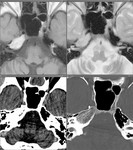

[画像メモ]小児の「特発性」腸重積の原因